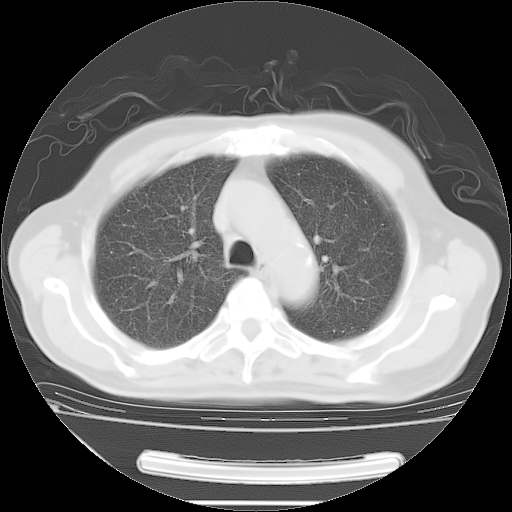

今天复查肺部CT,发现双肺广泛磨玻璃样改变。所以我把3月19日和5月9日相隔50天的肺部CT上传。请大家会诊。

5月9日肺部CT(在4月27日齐鲁医院肺部CT描述部分肺组织磨玻璃样改变,12天后肺组织广泛磨玻璃样改变)

2009年5月9日肺部CT

大致读了系列胸部CT:纵隔窗无明显异常,肺窗:从4、27至今:主要是双肺中下野外带可见毛玻璃样改变,目前处于急性肺泡炎阶段,至于原因考虑1、结替组织或胶原血管性疾病所致?2、恶性疾病如恶组在肺部所致的表现或细支气管肺泡癌?3、药物或其它原因如肺蛋白沉着症所致肺泡炎目前不太可能?总之,明天就去请我院的呼吸科、感染科、血液科和临免专家会诊哈。